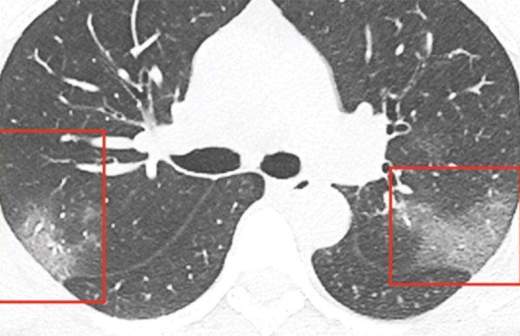

Число смертей от нового коронавируса в Китае возросло до 361, инфицированы 17 205 человек. Об этом сообщается в заявлении Государственного комитета по делам здравоохранения КНР, опубликованном в понедельник, 3 февраля.

Как следует из заявления ведомства, только в воскресенье в Китае было установлено 2829 новых случаев заболевания и 57 смертельных случаев.

Первая вспышка вирусной пневмонии, причиной которой оказался новый вид коронавируса, была зафиксирована в китайском городе Ухань в конце декабря 2019 года. Случаи заболевания зарегистрированы во всех регионах Китая.

Всемирная организация здравоохранения (ВОЗ) признала вспышку нового коронавируса чрезвычайной ситуацией международного масштаба.